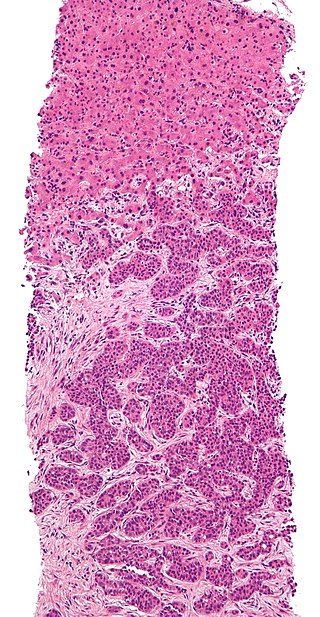

Hepatocyte apoptosis is a sign of inflammation, which affects the lobules of the liver and the portal tracts.

Cirrhosis is the last stage of liver damage and is marked by bands of fibrosis and hepatocyte regenerating nodules that disrupt the normal hepatic parenchyma.

Under the endothelial cells that line the sinusoids, stellate cells that are present in fibrosis are responsible for cirrhosis.